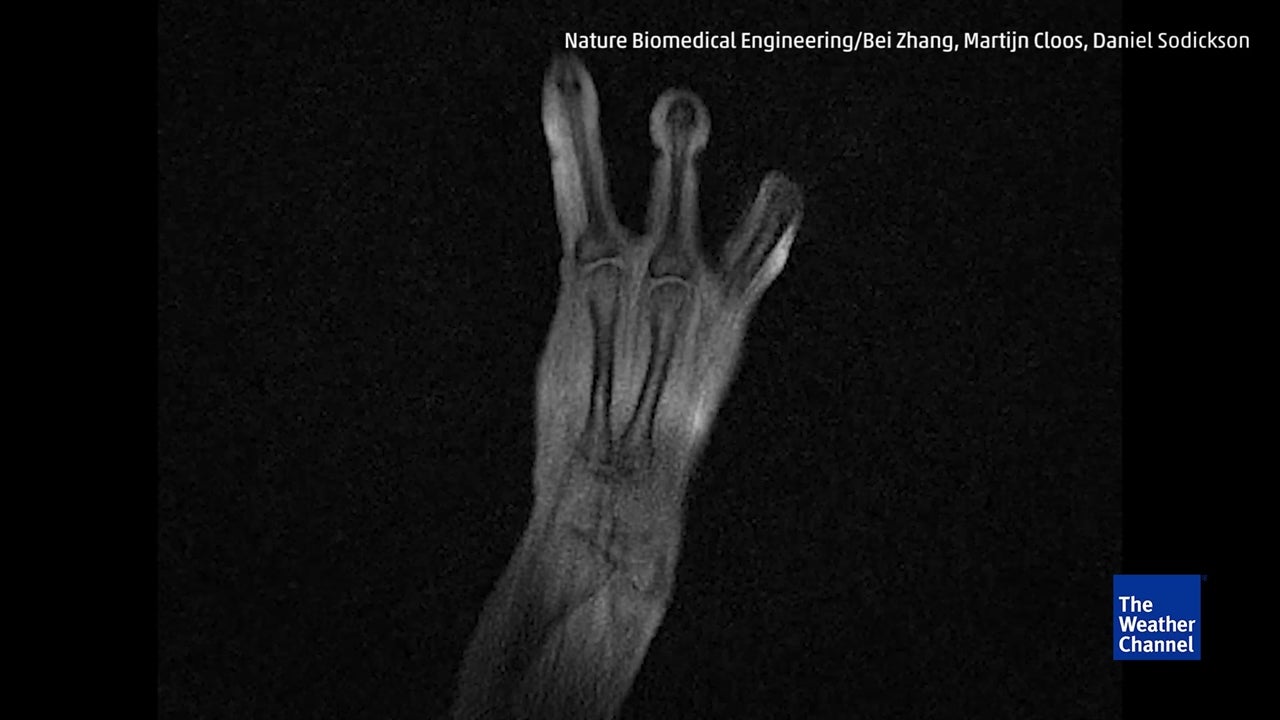

MRI Glove Captures Bones in Motion | The Weather Channel